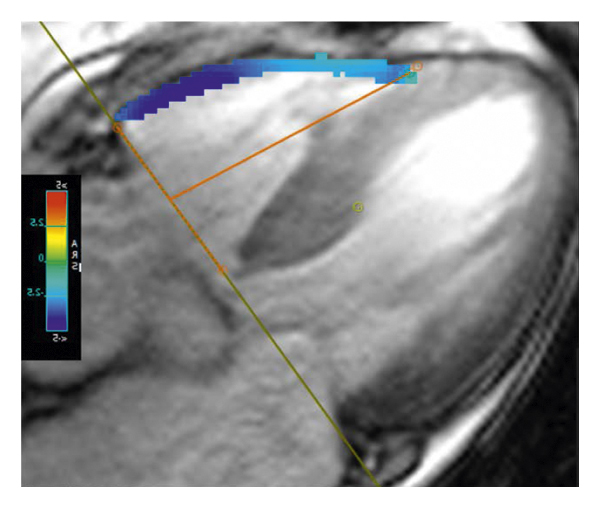

2.3. 이미징 분석모든 이미지 분석은 시중에서 판매되는 소프트웨어(cvi42, Circle Cardiovasic Imaging, Inc. Calgary, Canada)를 사용하여 수행되었습니다. 심장 기능을 측정하기 위해 심장내막 및 심외막 추적을 확장기 말기 및 수축기 말기의 직렬 단축 슬라이스에서 수동으로 수행했습니다. LV/RV 확장기말 용량(EDV), 수축기말 용량(ESV) 및 LV/RV 박출률을 포함한 전체 LV/RV 수축기 기능이 계산되었습니다. LV 및 RV 심근 스트레인 분석은 장축 4챔버 및 단축 슬라이스를 조직 추적 모듈에 로드하여 수행되었습니다(그림 1 (a) 및 1 (b)). RVT는 중실의 3회 측정하였고, 평균 두께를 계산하였다(도 1 (c) 및 1 (d)). GRPS(글로벌 라디칼 피크 변형), GLPS(글로벌 세로 피크 변형) 및 GCPS(글로벌 원주 피크 얼룩)를 포함하여 전역 특징 추적 매개변수가 자동으로 획득되었습니다. 최고 수축기 변형률(PSSR, 이완기부터 다음 수축기까지의 모든 단계에 대한 절대값의 최대 변형률)과 최고 확장기 변형률(PDSR, 수축기부터 다음 수축기까지 모든 단계에 대한 절대값의 최대 변형률)은 다음과 같습니다. 또한 분석했다. 양수 기호와 음수 기호는 서로 다른 동작 방향을 나타냅니다. 앞서 기술한 바와 같이[ 16 ], 정상적인 RVT 값은 7mm 이하로 정의되었다. 기준에 따라 CA 및 HCM 환자를 RV 비대(RVT >7 mm) 또는 RV 비대(RVT ≥7 mm) 환자에 따라 하위 그룹으로 나누었습니다.

(ㅏ) -

(비) -

(씨) -

(디)